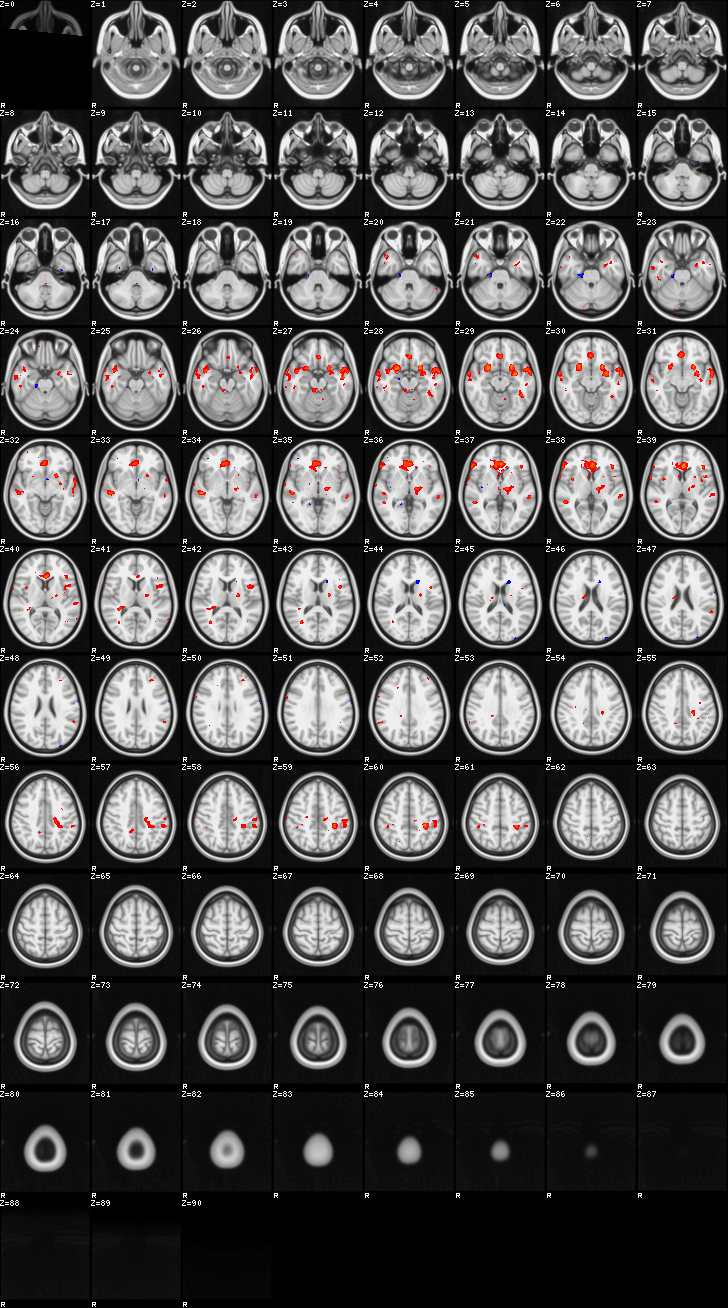

Mixed Effect (flame1)¶

ATM it is 8 subjects, 8 mm FWHM spatial smoothing, preliminary results only

Images thresholded abs value > 2.3 and colormap goes from 2.3 to 5 (red->yellow) or -2.3 to -5 (blue->lightblue)

Contrasts:

- FgtC

- Familiar > Control

- FltC

- Well – the opposite, and since both sides are plotted, it is just inverted colormap

00-FgtC¶